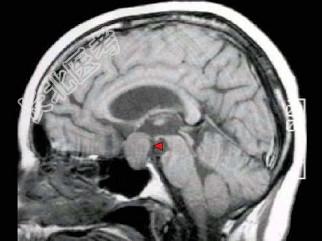

- 单项选择题男,37岁, 视力模糊,部分视野缺失, 伴有头痛、恶心数月,MRI检查如图, 最可能的诊断为 ( )

A、颅咽管瘤

B、脑膜瘤

C、蛛网膜囊肿

D、垂体瘤

E、表皮样囊肿